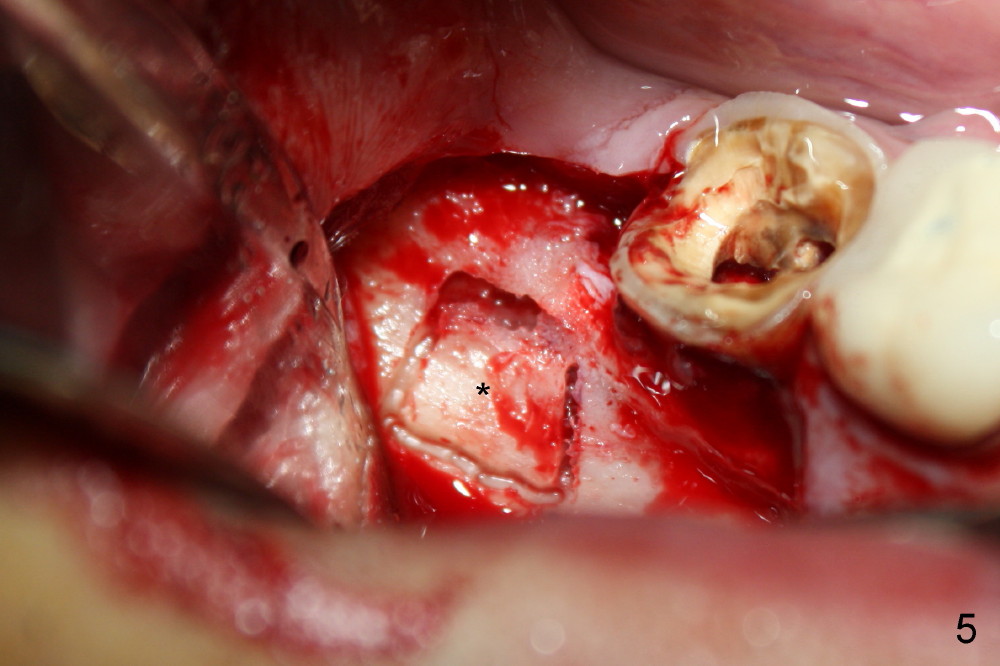

Immediate Implant Next to Dentigerous Cyst

A 47-year-old man requests restoring the tooth #31 (Fig.1). It appears

that the best option is an implant. A close look reveals a possible cyst

(arrowheads) associated with #32. On the day of surgery, a panoramic X-ray

is taken (Fig.2). The cyst is to be enucleated while an immediate implant

is to be placed in the mesial socket of #31. An incision is made as

indicated by Fig.3 arrowheads. The bone is resorbed on the top of the cyst

(Fig.4<). A bony window is made (Fig.5*) to expose the impacted tooth of